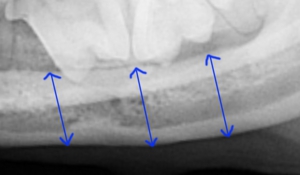

術後3ヶ月目の写真です。青の矢印で描出されているように下顎が再生されております。